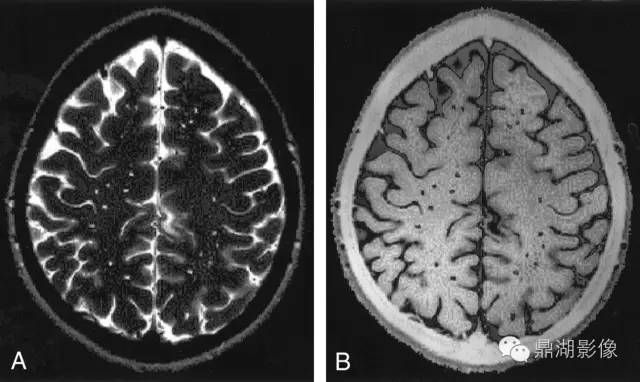

4.2.4 PVS

指南对PVS的定义为:穿过灰质或白质,与常见血管走行一致的充满液体的间隙。PVS扩张在MRI上主要表现为直径<3 mm的圆形、卵圆形或线形的,T1WI上低信号、T2WI上高信号(与脑脊液信号强度一致)、FLAIR上低信号、DWI上无弥散受限的病灶,通常边界清晰、无对比剂增强效应和占位效应。病灶形状取决于成像平面,成像平面与血管走行平行时呈线性,与血管走行垂直时呈圆形或卵圆形。该征象多见于基底节区靠近前联合附近、脑凸面皮层下、半卵圆中心、脑干及外囊,很少出现在小脑,常与假定血管源性的腔隙灶同时出现,需加以鉴别。普遍接受的用来区分两者的特点是PVS直径一般不超过3 mm,且在T2WI和FLAIR上不表现为围绕脑脊液样信号的环状高信号,除非间隙跨越白质高信号区。